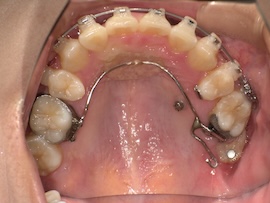

写真は撮っていないのでさらに1ヶ月後、

急に親知らずが出てきましたね。(笑)

無事に牽引ができたので、内側の装置も外れました。予定していたよりもかなり早く、牽引を始めてから約5ヶ月の時点です。